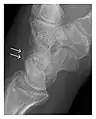

a

b

Figure 4: Dorsal triquetral fracture of the left wrist in a 30-year-old man after a trauma. (a) Anteroposterior radiograph shows a normal appearance. (b) Lateral radiograph of the same wrist demonstrates a chip fracture off the dorsal aspect of the triquetrum (arrow).[1]